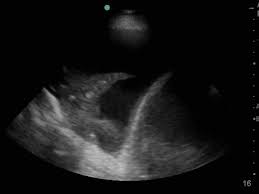

What is the most likely diagnosis?

Acute Hepatitis